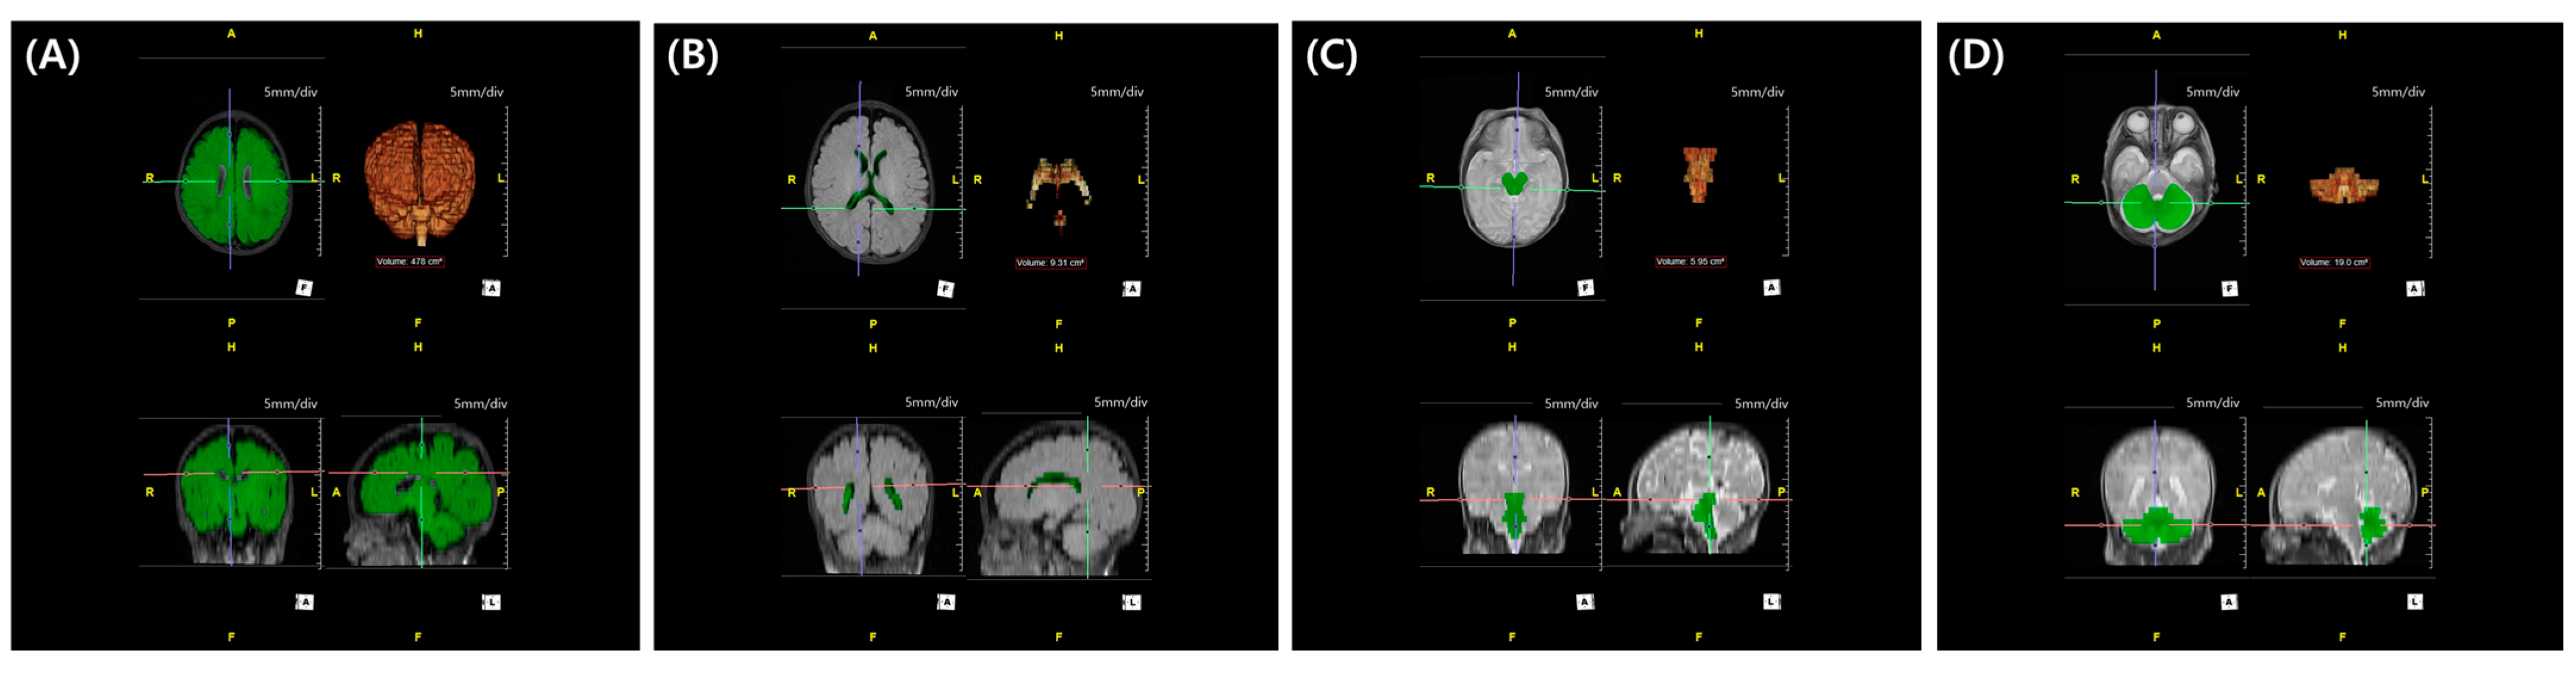

In our center, brain MRI is routinely performed in very preterm or VLBW infants to screen for white matter injuries. According to our protocol, MRI is recommended at TEA. However, if the infant is medically unstable, the scan is delayed. Conversely, if earlier imaging is clinically indicated, MRI may be performed prior to TEA. Minimizing the confounding effect of brain growth, we selected brain MRI scanned between the previously mentioned window period: obtained between 36+0 to 44+6 weeks of PMA. Axial fluid-attenuated-inversion-recovery and T2 MRI images (Figure 2) were annotated by a technician (TE) using a 3D workstation (Aquarius iNtuition, TeraRecon Inc., Durham, NC, USA) program. The results were reviewed and confirmed by a pediatric radiologist (ISA). The evaluators were blinded to the clinical outcomes. Based on these annotations, quantitative assessment (total brain volume, cerebral volume, cerebellar volume, brainstem volume, and ventricular volume) was performed. The segmented structures were reconstructed in 3D to confirm shape accuracy; an example is shown in Figure 3.

Figure 3.

Regional volume calculated through 3D workstation: 3D-reconstructed intracranial volume (A), 3D-reconstructed ventricle volume (B), 3D-reconstructed brain stem volume (C), and 3D-reconstructed cerebellar volume (D).